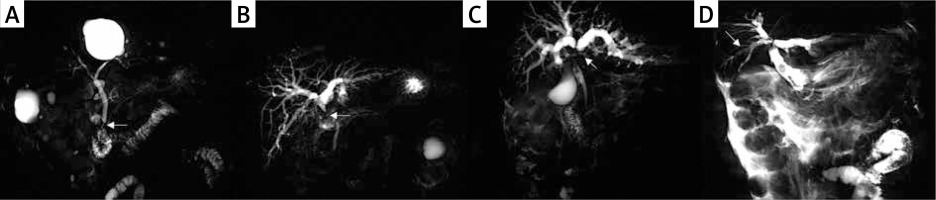

It is necessary and feasible to study the risk factors of POBS. First of all, POBS is universal. Biliary diseases are a large class of surgical diseases with a high incidence rate and a variety of types. Biliary stones are the most common benign diseases. According to the National Institute for Health and Care Excellence (NICE) consensus in 2016, 10–15% of British adults suffer from gallbladder stones and/or bile duct stones, 50% of symptomatic patients will have recurrent abdominal pain, fever, jaundice and other symptoms, and 1–2% of patients will have serious complications [15]. Cholangiocarcinoma is the most common malignant disease, originating from biliary epithelial cells. Its incidence rate is rising steadily worldwide, and it is currently listed as the second most common hepatobiliary tumor [16]. Because the hepatoduodenal ligament and its adjacent structures have an important position as a “crossroad”, the selection of surgical methods and the treatment of postoperative complications have become one of the key challenges faced by general surgeons. Postoperative biliary fistula, fluid accumulation in the operation area, bile duct infection, biliary bleeding, biliary stricture, etc. are common complications, which are related to the hospital stay, survival period and long-term prognosis of patients [17]. Secondly, the body damage of patients with biliary stricture is long-term and persistent. As one of the most common postoperative complications of the three major bile ducts, long-term retrohepatic bile duct obstruction of patients with biliary stricture can lead to liver fibrosis at different levels, thus affecting liver function for a long time, inducing liver failure and cirrhosis. Removing the obstruction can alleviate the process of liver fibrosis, but it cannot reverse fibrous hepatocytes [18]. In addition, hepatic duct stricture after surgery for intrahepatic calculi is an important risk factor for patients to have long-term complications, such as recurrent cholangitis, cirrhosis and cholangiocarcinoma [19], and bile duct stricture in different parts will also affect the occurrence of postoperative cholangitis. The incidence of postoperative stenosis cholangitis in the common hepatic duct or bile duct is higher than that in the single intrahepatic bile duct stricture [20]. Thirdly, similar with bile duct bleeding and infection, laboratory tests and imaging examinations can be confirmed in patients with POBS before secondary surgery. Although the current literature does not quantitatively determine the specific value of bile duct stricture in different parts, considering that the bile duct is a hollow organ, the recognized biliary stricture in the imaging field is still a qualitative diagnostic standard: namely, the thinning and narrowing of the downstream bile duct and the expansion of the upstream bile duct, and Bismuth classification is still considered as the gold standard for biliary stenosis classification [21]. Surgeons can evaluate the position and severity of stenosis of patients according to the changes of clinical, laboratory and imaging indicators, so as to timely intervene to avoid damage of liver function (Photo 1).

Photo 1

T-tube angiographic image of bile duct stricture after operation of benign biliary tract disease, with arrows indicating the position of stricture. A – Bismuth I, B – Bismuth II, C – Bismuth III, D – Bismuth IV